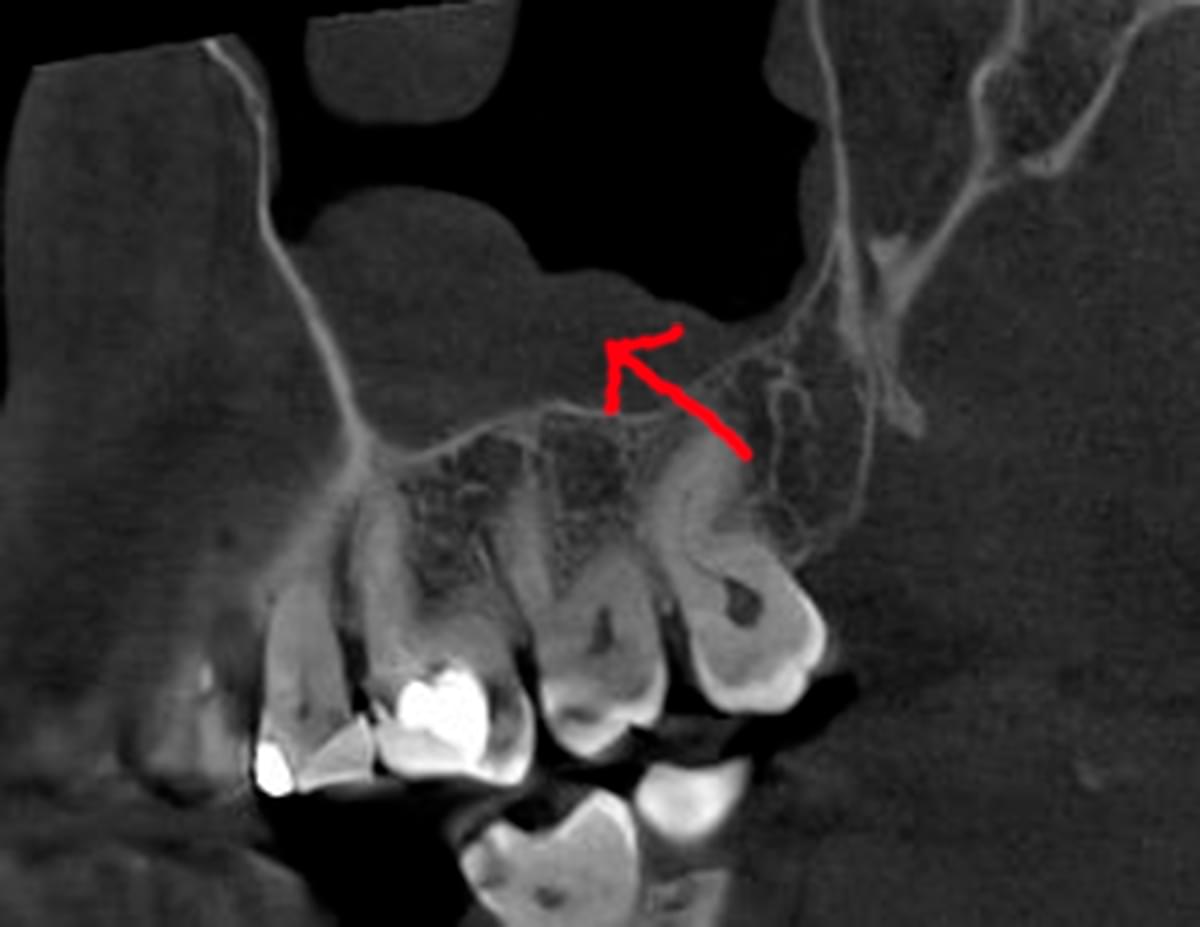

Головний недолік 2D-рентгену — це площинне зображення. Зуби, корені, щільна кістка та гайморові пазухи накладаються один на одного, створюючи «візуальний шум».

Візуальне порівняння (Кейс одного пацієнта)

Зуб — це не просто монолітний об'єкт, а складна система мікроканалів. На плоскому 2D-знімку вони часто перекривають один одного, створюючи ілюзію простої анатомії.

Непомічений канал — це джерело майбутньої інфекції та причина «загадкового» болю після лікування. Завдяки високій роздільній здатності обладнання MyRay, лікар бачить кожен мікронний канал ще до того, як візьме до рук інструмент.

Коли коріння «ховає сюрпризи» - Корені зубів часто мають складну кривизну, гачкоподібні закручення або розгалуження, які на звичайному 2D-знімку накладаються один на одного, створюючи ілюзію прямого каналу. На плоскій картинці неможливо побачити реальний об'єм та напрямок вигину, що критично важливо при видаленні «зубів мудрості» або ендодонтичному лікуванні. КТ MyRay дає змогу лікарю заздалегідь побачити 3D-геометрію кожного кореня, оцінити його близькість до нижньощелепного нерва чи гайморової пазухи та підібрати правильну тактику роботи. Це мінімізує ризики поломки інструменту в каналі або травмування сусідніх структур, перетворюючи складну хірургію на прогнозовану процедуру.

Часто причиною зубного болю є гайморит, і навпаки — причиною запалення пазух є хворий зуб. На звичайному знімку пазуха виглядає як темна пляма. На КТ ми бачимо стан слизової, наявність кіст або сторонніх тіл (наприклад, залишків пломбувального матеріалу), що критично важливо для правильного діагнозу.